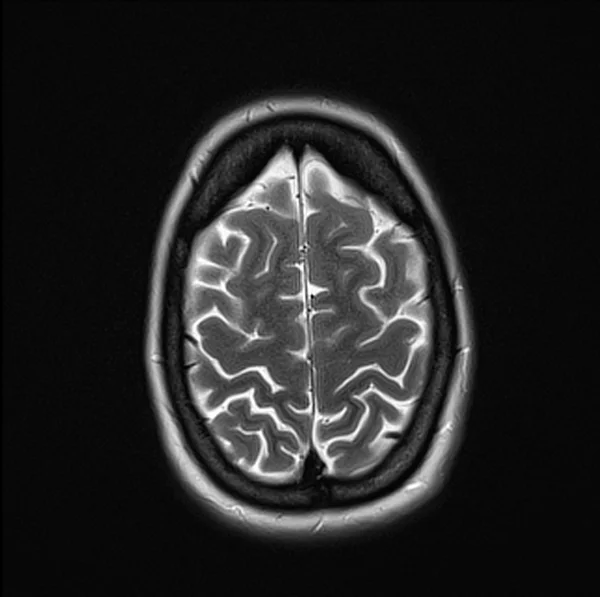

Brain MRI T2 axial images